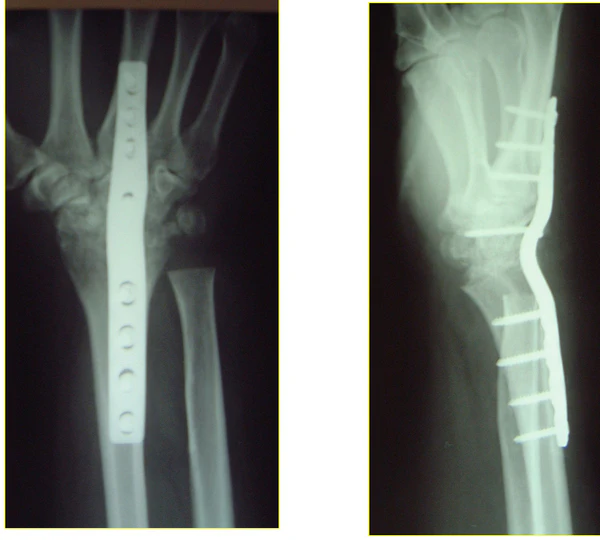

Хирургическое вмешательство обычно показано при смещённых или нестабильных переломах. Методы хирургического лечения включают открытую репозицию с внутренней фиксацией, внешнюю фиксацию, чрескожную фиксацию штифтами или их комбинацию. Выбор метода оперативного лечения часто определяется типом перелома, который можно в целом разделить на три группы: частичные суставные переломы, смещённые суставные переломы и метафизарные нестабильные внесуставные или минимальные суставные переломы[1].

В лечении достигнуты значительные успехи. Два новых метода лечения — это фрагмент-специфическая фиксация и угловая ладонная пластина. Эти методы предполагают фиксацию, достаточно жёсткую для обеспечения практически немедленной подвижности, с целью минимизации скованности и улучшения конечной функции; улучшения конечного результата при ранней мобилизации (до 6 недель после хирургической фиксации) не наблюдалось. Хотя восстановление положения лучезапястного сустава считается очевидным, точная величина угла, укорочения и внутрисуставного зазора/ступеньки, влияющих на конечную функцию, неизвестна. Выравнивание также важно, так как это может быть источником боли и потери вращательной функции после окончательного заживления и максимального восстановления[1].